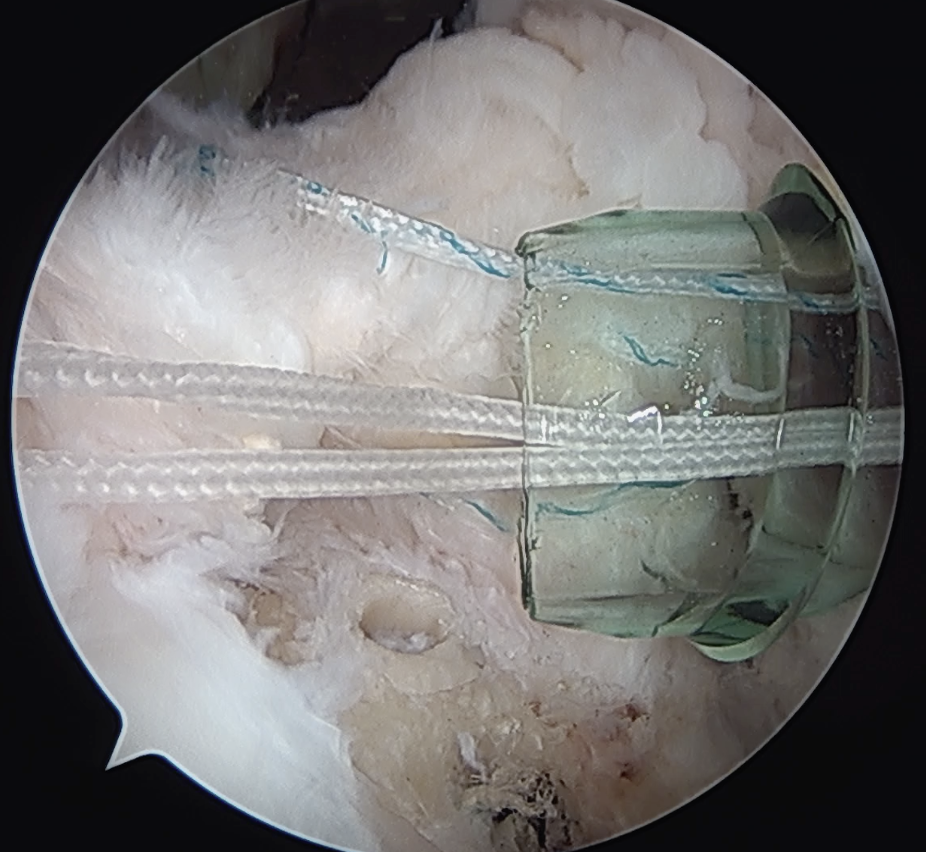

Double row anchors

- medial anchor row at articular margin and tie through medial cuff

- lateral anchor row at lateral footprint used to secure sutures

- increase surface area of cuff repaired to foot print

Trans-osseous equivalent / suture bridge

- cross sutures from medial row to lateral row

- increase contact between cuff and footprint

Double row / suture bridge

- use medial row sutures

- secure in knotless lateral row anchors